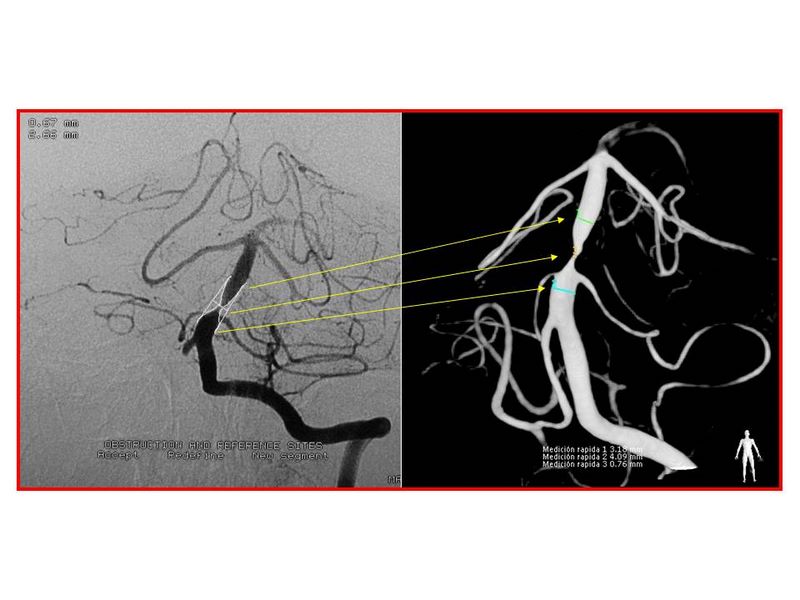

Estenosis Basilar